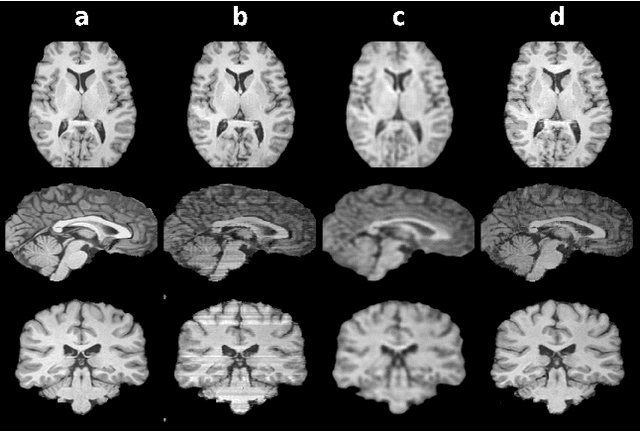

Abstract:Magnetic resonance imaging (MRI) offers the flexibility to image a given anatomic volume under a multitude of tissue contrasts. Yet, scan time considerations put stringent limits on the quality and diversity of MRI data. The gold-standard approach to alleviate this limitation is to recover high-quality images from data undersampled across various dimensions such as the Fourier domain or contrast sets. A central divide among recovery methods is whether the anatomy is processed per volume or per cross-section. Volumetric models offer enhanced capture of global contextual information, but they can suffer from suboptimal learning due to elevated model complexity. Cross-sectional models with lower complexity offer improved learning behavior, yet they ignore contextual information across the longitudinal dimension of the volume. Here, we introduce a novel data-efficient progressively volumetrized generative model (ProvoGAN) that decomposes complex volumetric image recovery tasks into a series of simpler cross-sectional tasks across individual rectilinear dimensions. ProvoGAN effectively captures global context and recovers fine-structural details across all dimensions, while maintaining low model complexity and data-efficiency advantages of cross-sectional models. Comprehensive demonstrations on mainstream MRI reconstruction and synthesis tasks show that ProvoGAN yields superior performance to state-of-the-art volumetric and cross-sectional models.